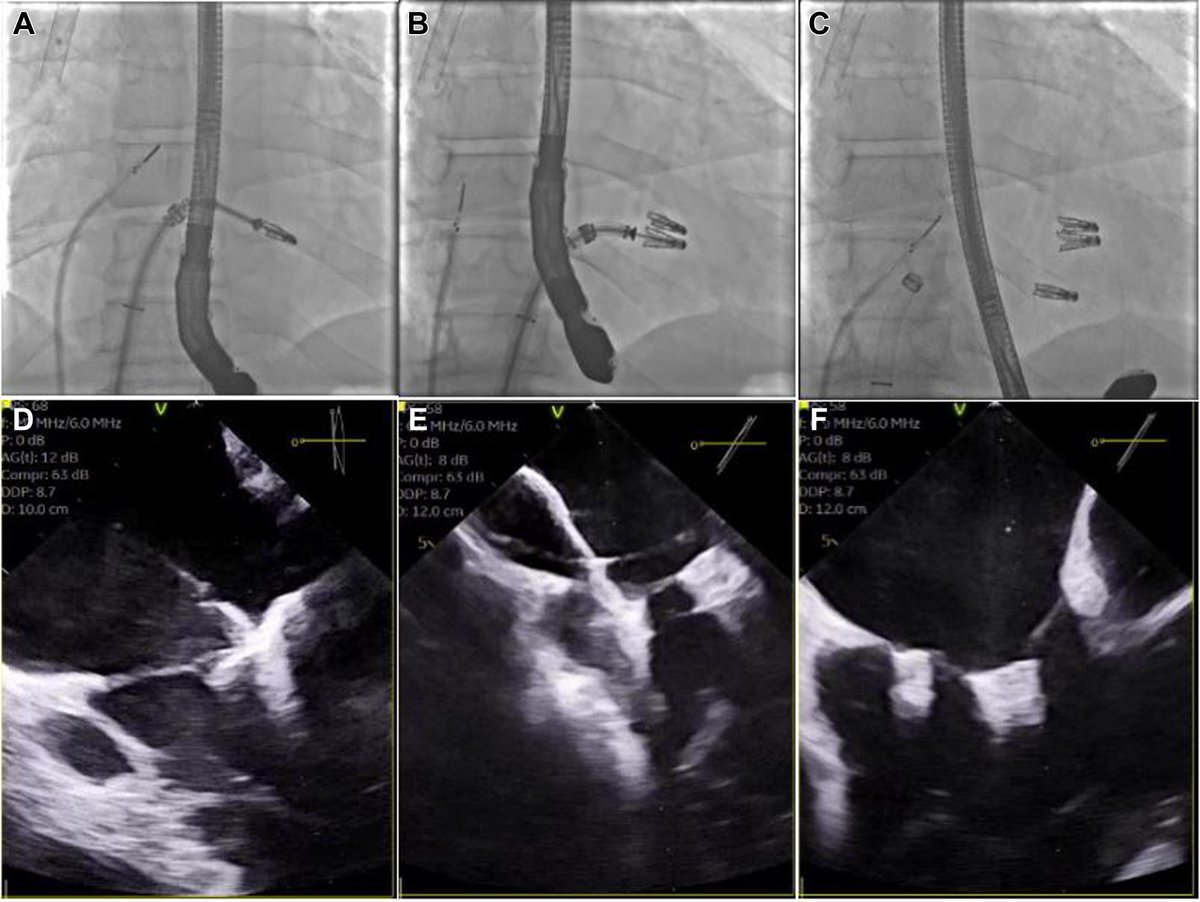

Single TriClip Steerable Guide for Combined MitraClip and TriClip Transcatheter Edge-to-Edge Repair (STric-TEER): A Multicenter Registry presented @PCRonline #PCRLV and published simultaneously @AlexLee_MD @GilbertTangMD @EuroInterventio #EuroPCR https://t.co/biXFPaurrd